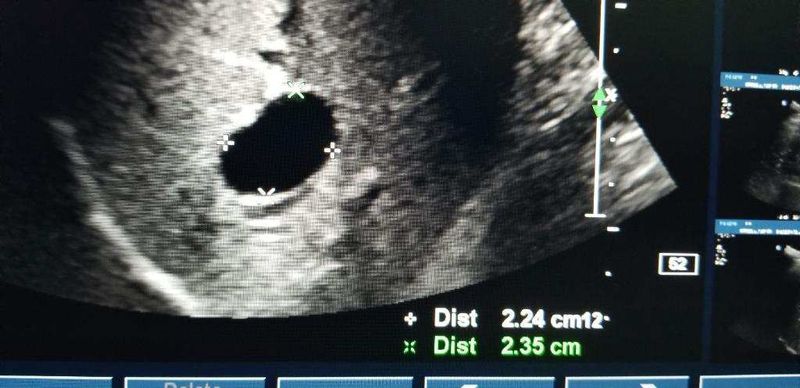

Liver ultrasound

It should be an hepatic cyst.For further investigation and treatment,ask for a surgical consultation.